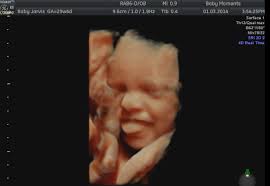

Sweet Baby Face 3d 4d Ultrasound

Sweet Baby Face 3d 4d Ultrasound. Book an appointment in Louisville or Elizabeth today. We Specialize in 4DHD Ultrasound 3D Ultrasound Photography and Baby Boutique items.

We Specialize in 4DHD Ultrasound 3D Ultrasound Photography and Baby Boutique items. Washington Fort Knox Radcliff Shepherdsville Seymour Cincinnati Lexington Elizabethtown Cecilia Corydon Owensboro Indianapolis and Salem. Sweet Baby Face is a 3D 4D Ultrasound and Baby Boutique in Louisville Elizabethtown KY.

Sweet Baby Faces Ultrasound Studio. The entire scanning session video will be provided via email for unlimited sharing with friends and family. 1479 likes 26 talking about this 691 were here. Now you can see your baby up close and personal with a 3D4D HD ultrasound from Sweet Baby Face.